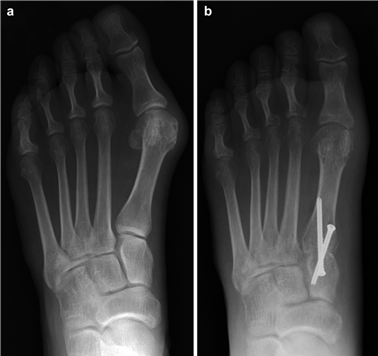

Weight-bearing anteroposterior (AP), lateral, and sesamoid axial radiographs are mandatory. On the AP view, the surgeon measures the Hallux Valgus Angle (HVA, normal < 15°), the Intermetatarsal Angle (IMA, normal < 9°), and the Distal Metatarsal Articular Angle (DMAA). The lateral view is scrutinized for Meary's angle (talo-first metatarsal angle) to identify midfoot collapse, as well as the presence of dorsal osteophytes indicative of hallux rigidus. The sesamoid axial view is critical for assessing the degree of sesamoid subluxation and the integrity of the crista.

Clinical & Radiographic Imaging Archive